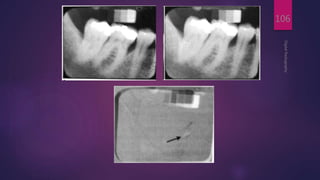

 Dental subtraction radiography (Ruttimann et al, 1981)

 When two images of the same object are registered and

 The strength of digital subtraction radiography (DSR) is

DigitalRadiography

106